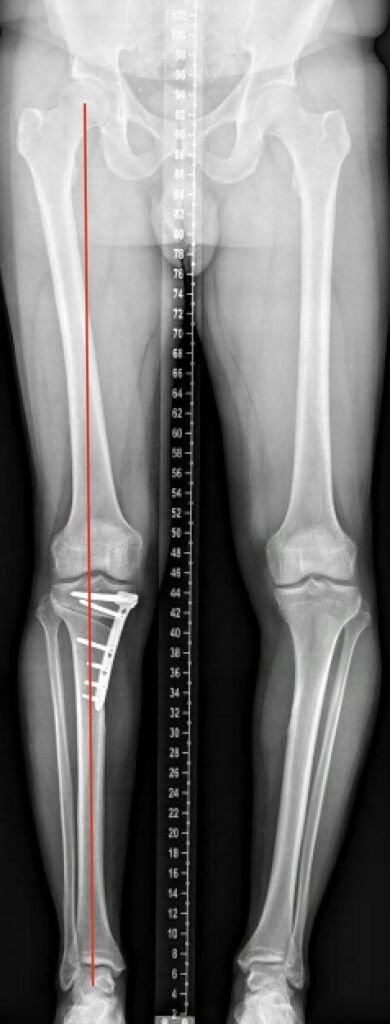

Varus

Post-operatieve foto na een open wig tibia osteotomie.

Het bot wordt ingezaagd tot aan het scharnier (1), daarna wordt er een opening gemaakt tussen de bot helften, de wig (2), de bot delen worden op hun plek gehouden door een plaat (3).